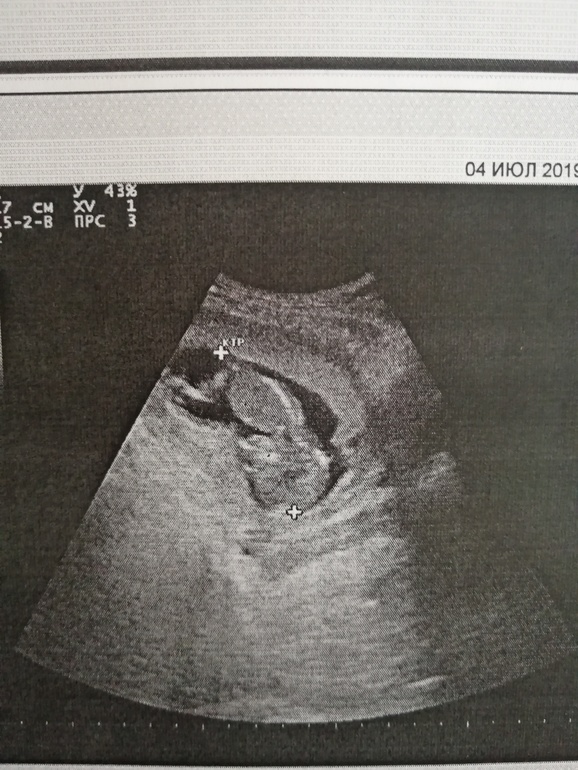

Добрый вечер мамуськи) сделала и я сегодня долгожданный 1 скрининг. Ура)) 12 нед. и 5 дней. ПДР 11 января 2020г. Вес 55 г. Женщина которая делала УЗИ, мне не очень понравилась, слова не вытянишь. Я как и многие тут не понимаю снимки, точнее не вижу кто, мальчик или девочка)) Но знаю точно, что в группе есть девочки которые понимают. Помогите понять пожалуйста)) кого вы видите.

По 1му фото предположу пацана. Но не факт. На остальных вообще ниче не видно.

На фото к сожалению не видно бугорка. Поздравляю с удачным скринингом. А кровь скоро будет готова? Сколько делают. У нас через неделю скрининг.

К сожалению полового бугорка не видно (